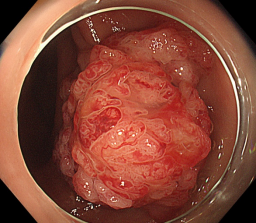

消化道早癌的病例展示(经内镜手术或活检证实):

胃角的腺癌

胃窦的微小腺癌

胃窦印戒细胞癌

十二指肠降段早癌